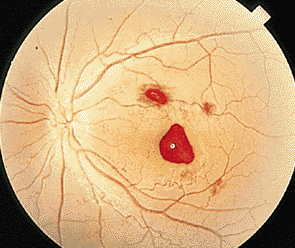

對于很多患者而言,玻璃體變性主要原因就是隨著年齡不斷增加,新陳代謝不斷變緩,使得玻璃體自身變性。比如像星狀玻璃體變性,常常見于50歲以上,不過它只是引起視力的不適,并不會導(dǎo)致視力下降。因為玻璃體內(nèi)新陳代謝緩慢,而出現(xiàn)了含鈣的脂質(zhì)白色小球。而玻璃體變性中更為嚴(yán)重的是出現(xiàn)液化現(xiàn)象,特別是閃輝性玻璃體液化,由于嚴(yán)重眼外傷和手術(shù)后眼內(nèi)出血導(dǎo)致的玻璃體或前房會出現(xiàn)無數(shù)黃白色和其他顏色的膽固醇結(jié)晶。

對于玻璃體混濁這樣復(fù)雜的癥狀,一般的眼科醫(yī)院無法根治,由于眼睛玻璃體的特殊性,目前尚無有玻璃體變性的特效藥,只能經(jīng)過長期的治療和鞏固,使得玻璃體不會出現(xiàn)其他病變。所以對于病情較為嚴(yán)重的玻璃體變性患者而言,就像因為變性引發(fā)的視網(wǎng)膜剝離或玻璃體出血等等,這些會出現(xiàn)視力嚴(yán)重減退,眼睛發(fā)紅、疼痛、畏光等等,一定要到專業(yè)的眼科醫(yī)院進行醫(yī)治,比如在廈門眼科醫(yī)院的眼底??疲D陙沓搜鄣撞≈?,玻璃體變性治療領(lǐng)域在全國也是處于領(lǐng)先位置。